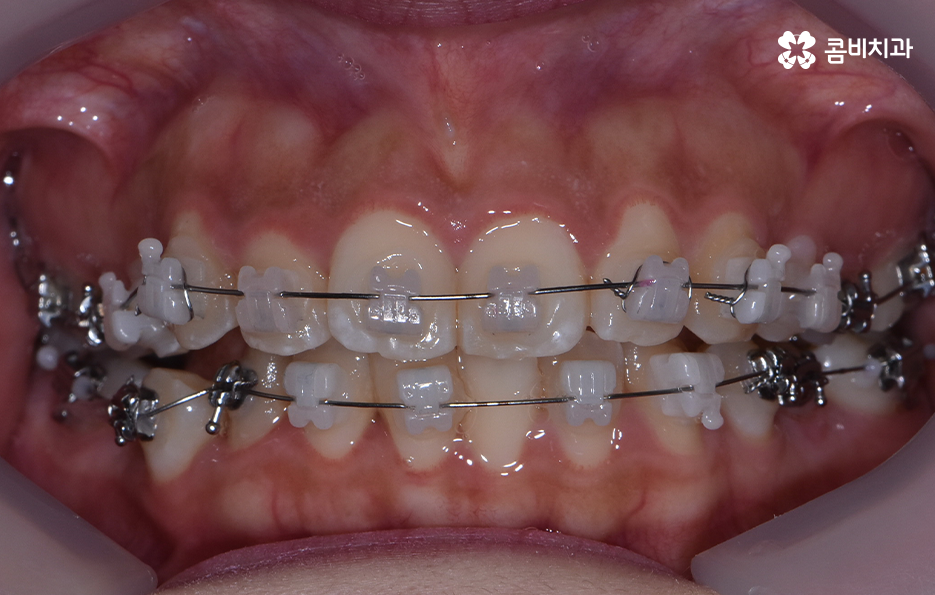

교정을 위해 치과에 가보시면 3D CT 등을 활용하여 3차원 정밀 분석을 통한 치료 후 시뮬레이션 결과까지 직접 보면서 확인할 수 있는데요. 발치 교정을 하면 비발치 교정에 비해서 얼굴 변화가 보다 크기 때문에 치료 후 결과에 대한 예측은 매우 중요한 과정으로 볼 수 있어요

치아교정은 한 번 시작하면 중간에 쉽게 바꿀 수도 없고 어렵게 결심하는 만큼 장기적인 관점에서 치료 계획을 꼼꼼하게 세워야 할 필요가 있는데요. 덧니 발치 교정에 있어서도 단지 치열만이 아니라 치아교정 결과에 있어서 입술 라인과 얼굴형과의 조화까지 생각하고 당연히 교합도 잘 고려하여 발치 여부를 판단한다고 보시면 좋을 거예요